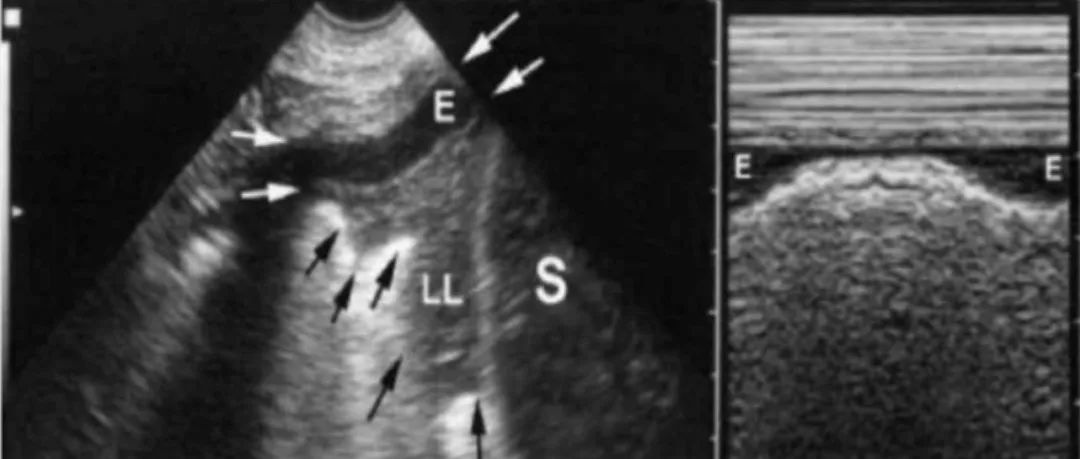

超声下胸腔积液的三种征象胸腔积液在重症患者中常见,本期力学笃行,小编带大家认识在超声下胸腔积液的三种征象:四边形征、正弦波征、水母征。四边形征胸腔积液时将胸膜线与肺表面分离,与上下肋骨的声影一起构成四边形的形状。正弦波征在B超模式下发现胸腔积液时,通过M超扫查可发现,肺表面线随呼吸运动向胸膜线方向运动而呈现类似正弦波样改变。水母征在胸腔大量积液时同时伴有压缩性肺不张情况中,不张肺在胸腔积液中“水母“样“游泳”的现象。...